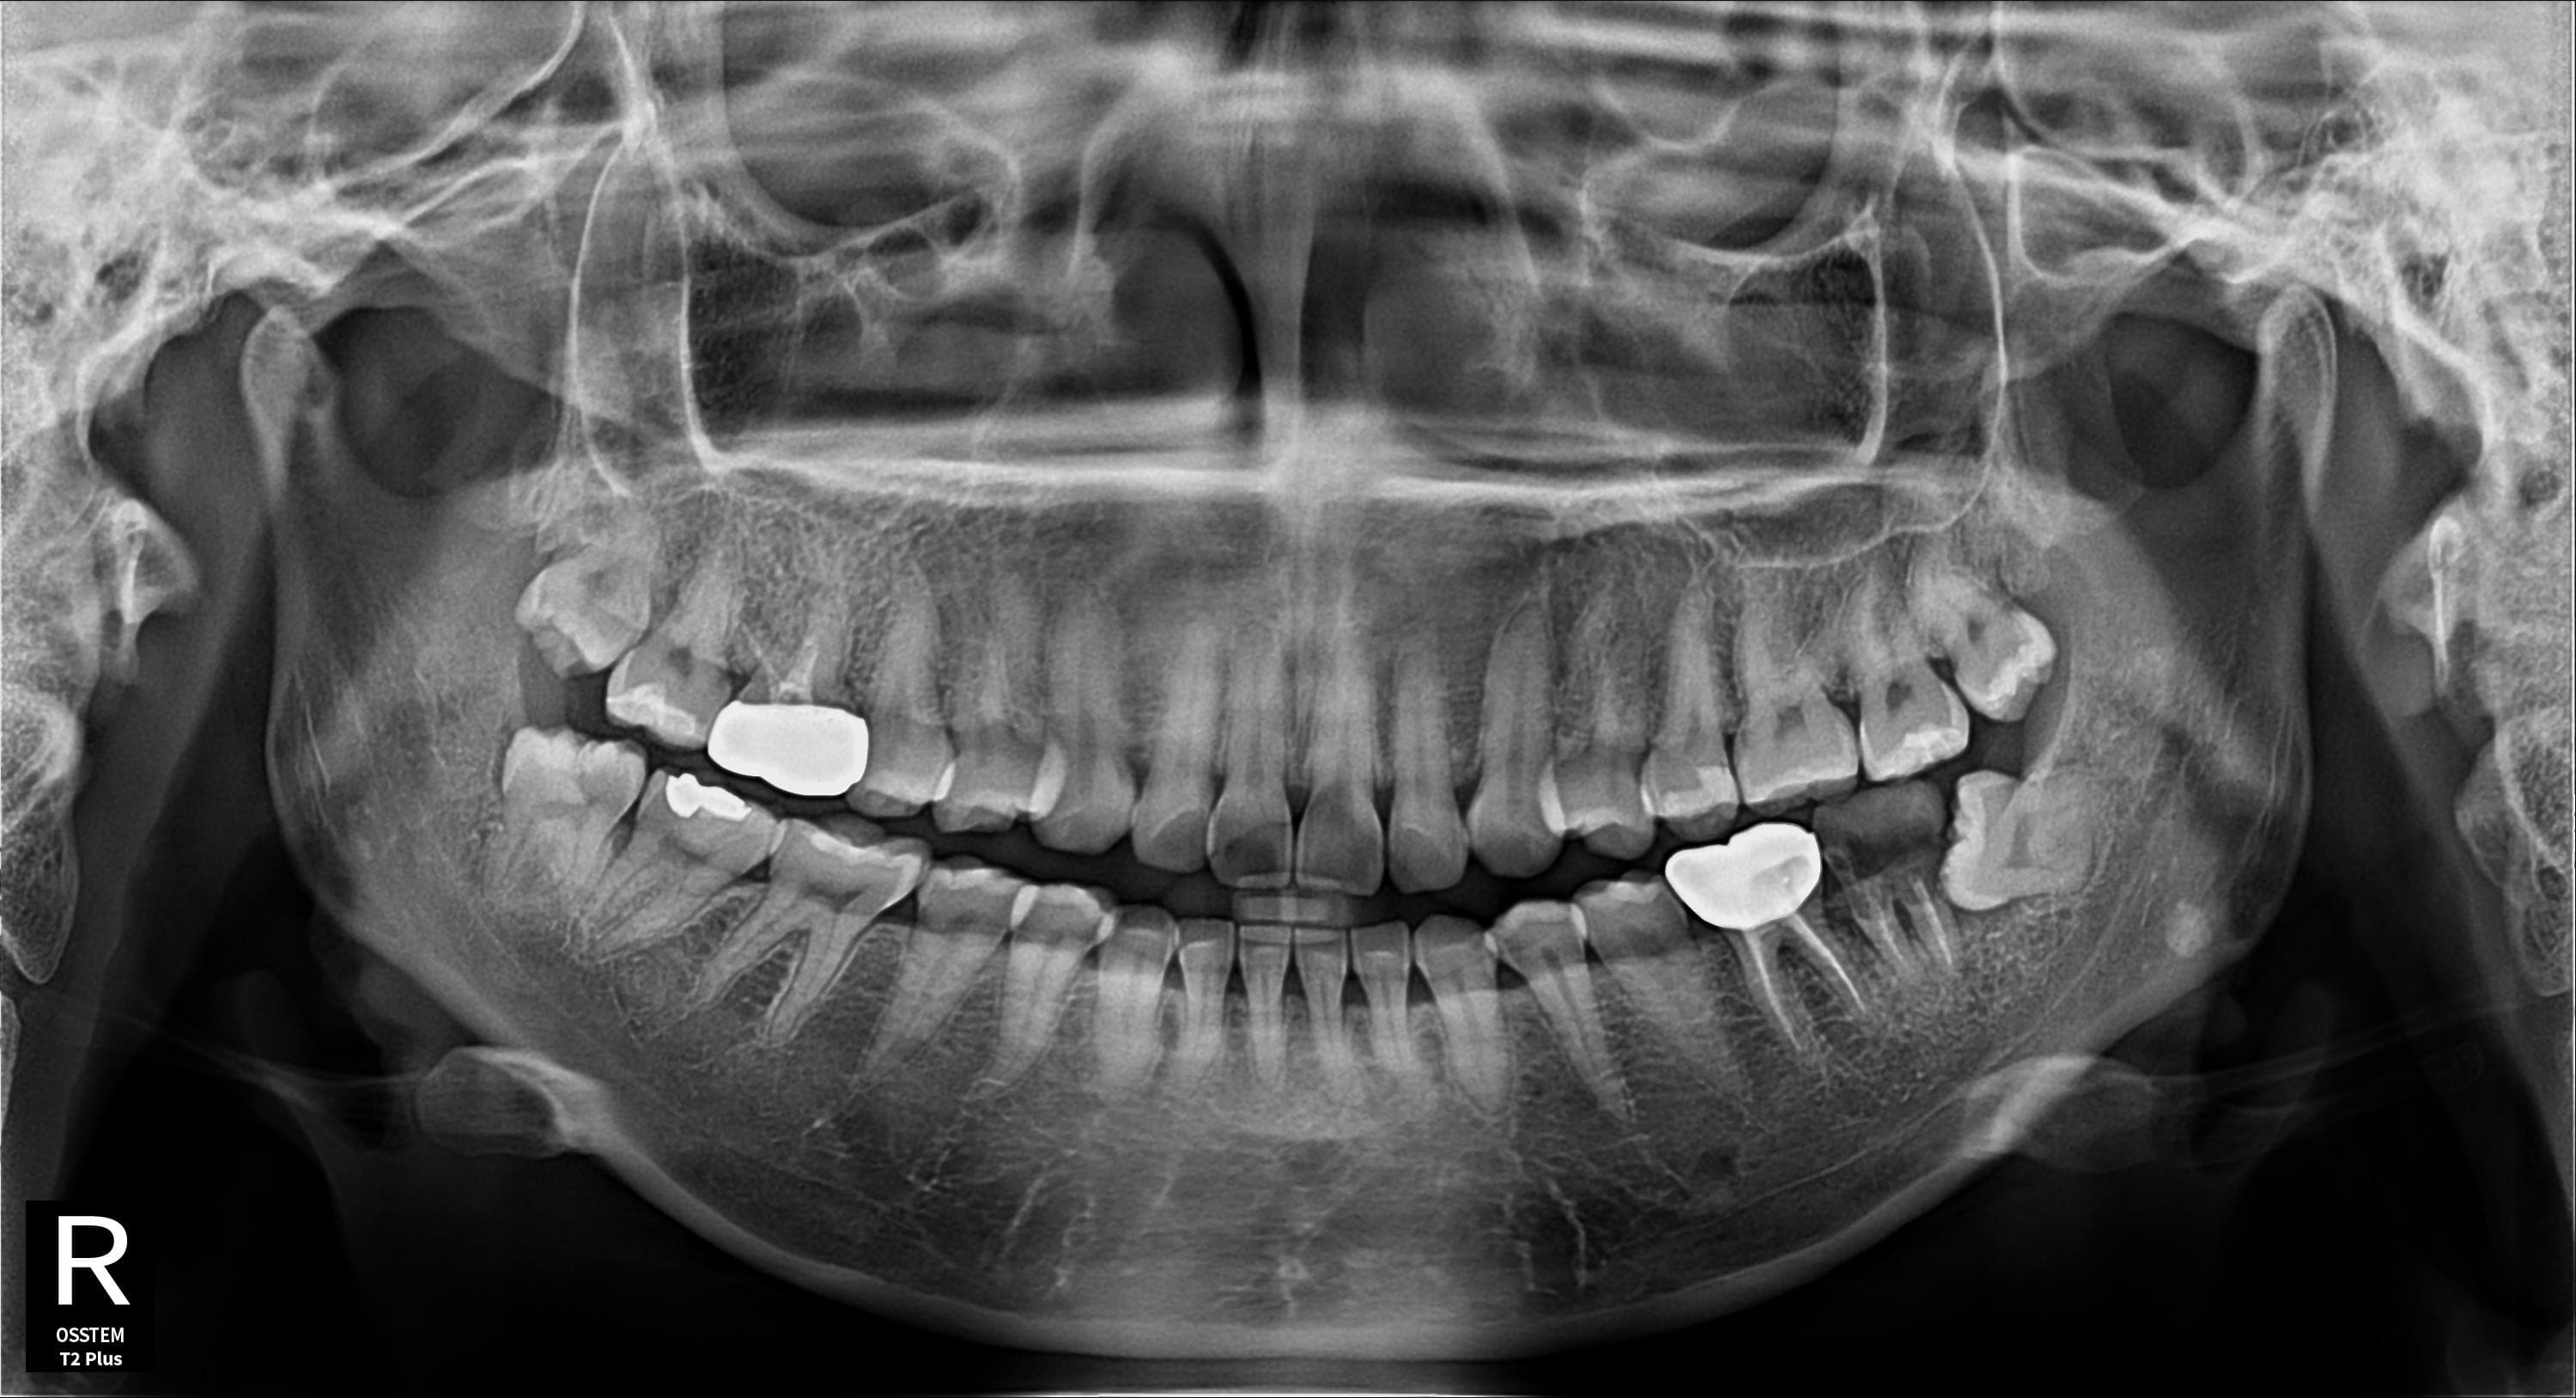

RISK LEVELS

사랑니 상태별 위험도

상태에 따라 발치 시기와 방법이 달라집니다

고위험

완전매복 사랑니

낭종 형성 가능성이 있어 조기 발치가 필요합니다

치근만곡 사랑니

뿌리가 구부러져 있어 발치 난이도가 높습니다

즉시 처치 필요

수평매복 사랑니

앞 치아를 밀어 치열 불균형과 충치를 유발합니다